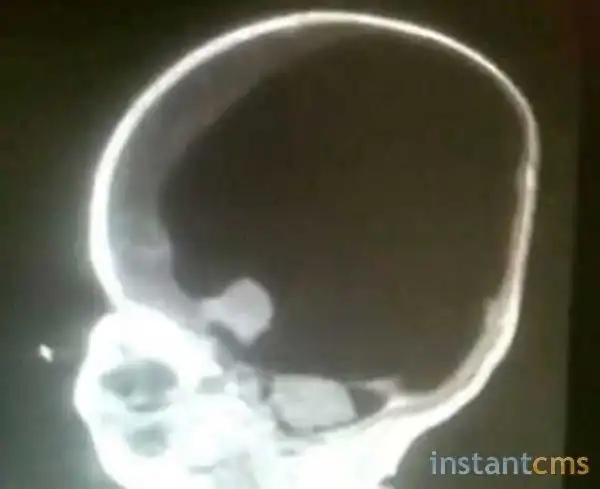

Родившись, 6 марта 2012 года, Ной вздохнул и даже заплакал. У ребенка оказались очень редкие хромосомные аномалии - практически отсутствовал мозг, также наблюдалось расщепление позвоночника. Врачи сообщили, что не смогут зашить отверстие, так как оно слишком большое. Нижняя часть туловища оказалась парализована. Шансов на выживание практически не было, семья готовилась к похоронам и даже купила гроб малышу.

Спустя десять дней после рождения, мать с ребенком выписали из больницы, но им приходилось постоянно посещать медицинский центр, чтобы откачивать жидкость из мозга мальчика.